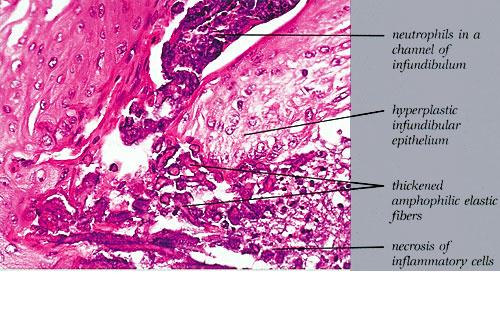

Elastosis perforans serpiginosa = المران الثاقب الزاحف